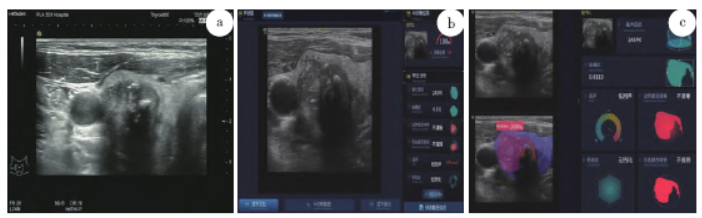

心脏移植受者行甲状腺癌根治术的围手术期管理(附1例报告)

病史摘要:44岁男性,体检发现甲状腺结节4月余入院。有高血压病史12年余,扩张性心肌病病史7年余且5年前出现心衰,于2022 - 03 - 12行心脏移植手术并进行免疫抑制治疗。诊疗过程:术前多学科会诊拟定甲状腺癌根治术。麻醉管理方面,入室后进行多项监测并建立通路,采用多种药物诱导麻醉、维持麻醉并备用心血管活性药物。术中行甲状腺癌根治术,见甲状腺右叶肿物,术后转入麻醉恢复室再转至外